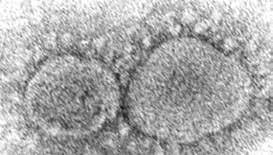

La COVID-19 se convirtió en la pandemia que paralizó ciudades

El 11 de marzo de 2020, la Organización

Mundial de la Salud otorgó la categoría de pandemia a la enfermedad de COVID-19

En los últimos días de 2019, un brote de ‘gripa’ en Wuhan, China, alarmó a ese país; primero, un resfriado muy fuerte que provocó rápidamente la muerte de algunos de los enfermeros.

El virus de SARS-CoV-2

nacía en esa pequeña ciudad del Oriente sin imaginar las consecuencias que tendría en el mundo, mismas que, a la fecha, siguen presentes en diversos países. La nueva cepa, que entonces era desconocida, se propagó rápidamente a los países europeos, después a

América con escala en México dos meses después.

Por la forma de contagio y, sobre todo, por la rapidez de su avance, el 11 de marzo de 2020, la Organización Mundial de la Salud (OMS) elevó a la categoría de pandemia la COVID-19.

Ese mismo día, el 11 de marzo de hace tres años, se confirmó el primer caso de la enfermedad en Querétaro; desde entonces, se contabilizan 6 mil 936 defunciones en la entidad y 188

mil 223 contagios.

EL CONFINAMIENTO

A medida que la enfermedad avanzaba y sin tener datos exactos sobre su peligrosidad, los gobiernos en el mundo establecieron el confinamiento como la medida más segura para evitar los contagios y, por ende, los fallecimientos.

La primera ciudad en ser confinada fue Wuhan, China, en enero de 2020; a partir de ahí, de forma gradual, lo hicie-

LOS NÚMEROS A ESCALA GLOBAL

A partir de la vacunación masiva en el mundo, en el último trimestre de 2020, se logró avanzar en el combate a la enfermedad, principalmente con la disminución de la sintomatología que, a su vez, ayudó a aminorar los cuadros graves y, con ello, la mortalidad.